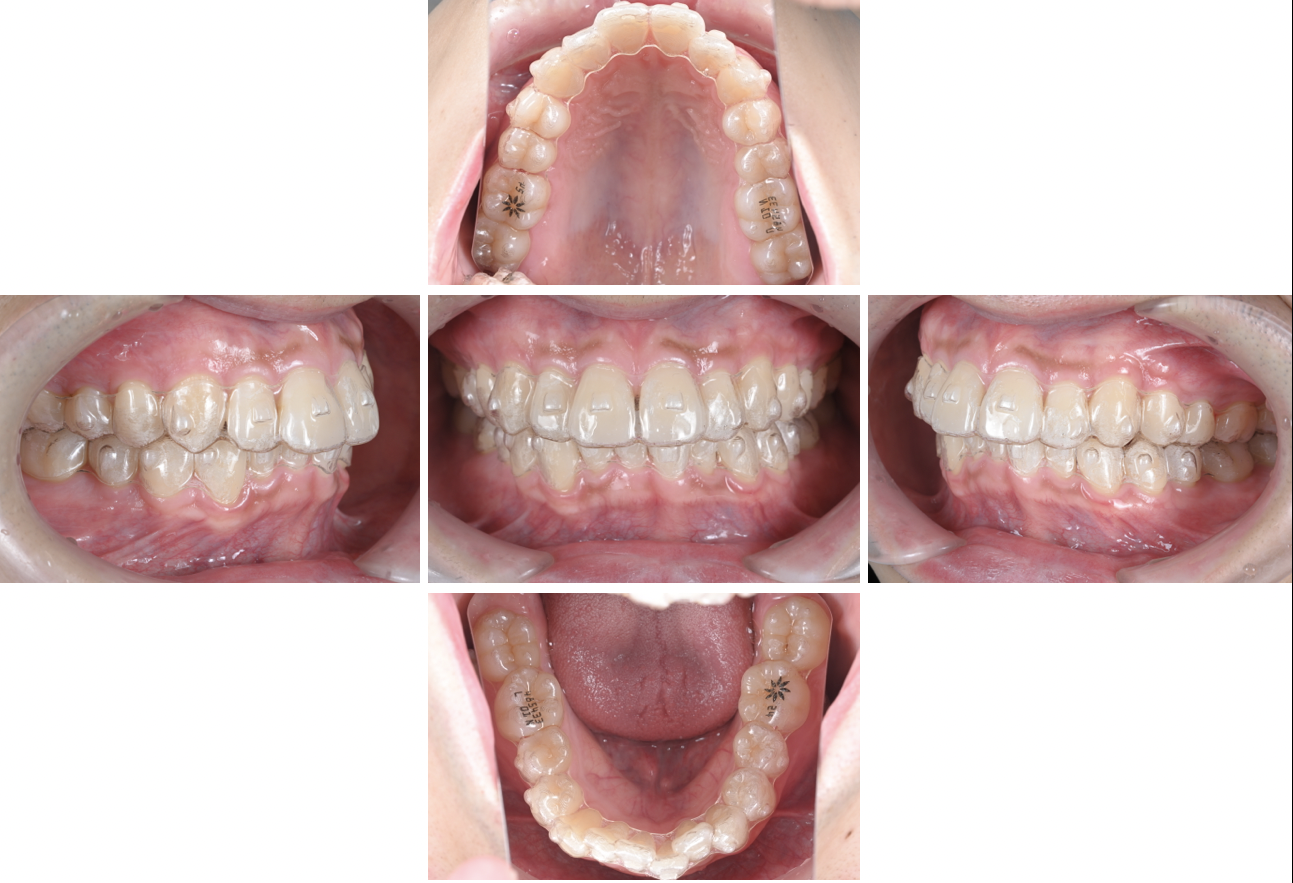

《マウスピース矯正中》

マウスピース矯正の治療途中です。

透明で、目立ちにくいのが特徴です。